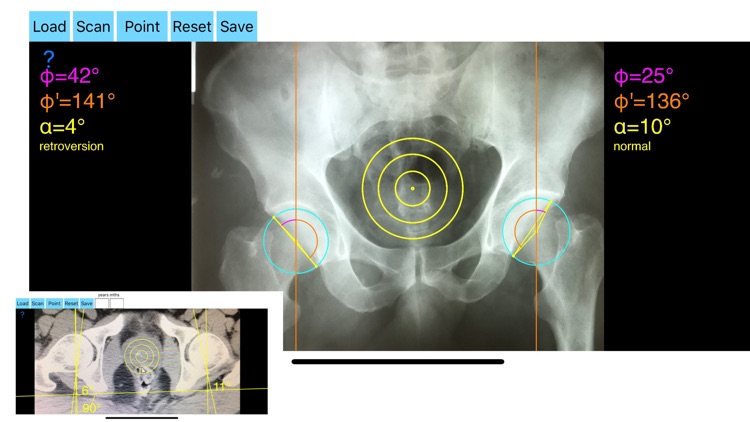

AcetabularAnteversionApp screenshot-1

Acetabular version is conventionally evaluated on CT scans but excessive radiation doses associated with routine use of computed tomography (CT). An objective radiographic tool which provides measurements comparable in accuracy to CT measurements has been developed by Dr. Hefti (Nomogram).Tedious and time-consuming calculation has to be done in simple X-rays in order to calculate the acetabular anteversion. The primary goal of this App is to help determine radiographic values of acetabular anteversion in a practice in a blink of an eye and avoiding CT scans.

-By marking certain points in a simple standard AP pelvic radiograph, geometric parameters are being calculated. The App computes the acetabular anteversion based on a pelvic AP radiograph. The angle of anteversion is calculated through the formula according to Heftis nomogram. The acetabular orientation (anteversion/retroversion) is determine by the app by the measurement of the angles between the center of the femoral head and the anterior (φ) and posterior (φ’) acetabular rim.

Once you choose correctly the anterior and posterior acetabular rims the app calculates the acetabular anteversion based on nomogram.

-The data are printed over to screen so each case can easily assessed